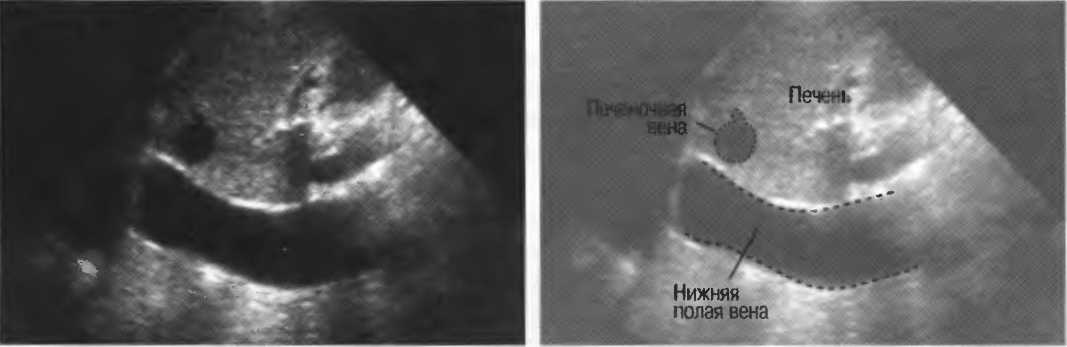

- Печеночные вены диаметром всего 3 мм должны визуализироваться при сканировании под углом 45° к поверхности нормальной печени (рис. 25).

Рис.25. Аппарат хорошего качества должен позволять визуализировать печеночные вены диаметром 3 мм. Этот тест может регулярно использоваться для контроля качества изображения.